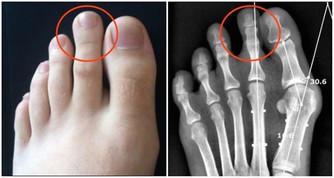

後來到另一家醫院檢查,最後確診為圓錐角膜。

圓錐角膜的最終結果就是角膜移植,

因而角膜會逐漸變尖,最終形成圓錐角膜,圓錐角膜的後果是使視力永遠喪失。

實行了LASIK後所產生的圓錐角膜目前在醫學上被認為是絕症,最後只能用角膜移植來解決問題!